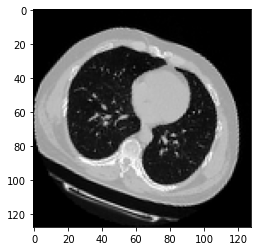

翻译 深度学习对CT扫描中是否存在病毒性肺炎的预测

此示例将显示构建3D卷积神经网络(CNN)以预测计算机断层扫描(CT)扫描中是否存在病毒性肺炎所需的步骤。2D CNN通常用于处理RGB图像(3个通道)。3D CNN只是3D等价物:它以3D卷或2D帧序列(例如CT扫描中的切片)作为输入,3D CNN是学习体积数据表示的强大模型。